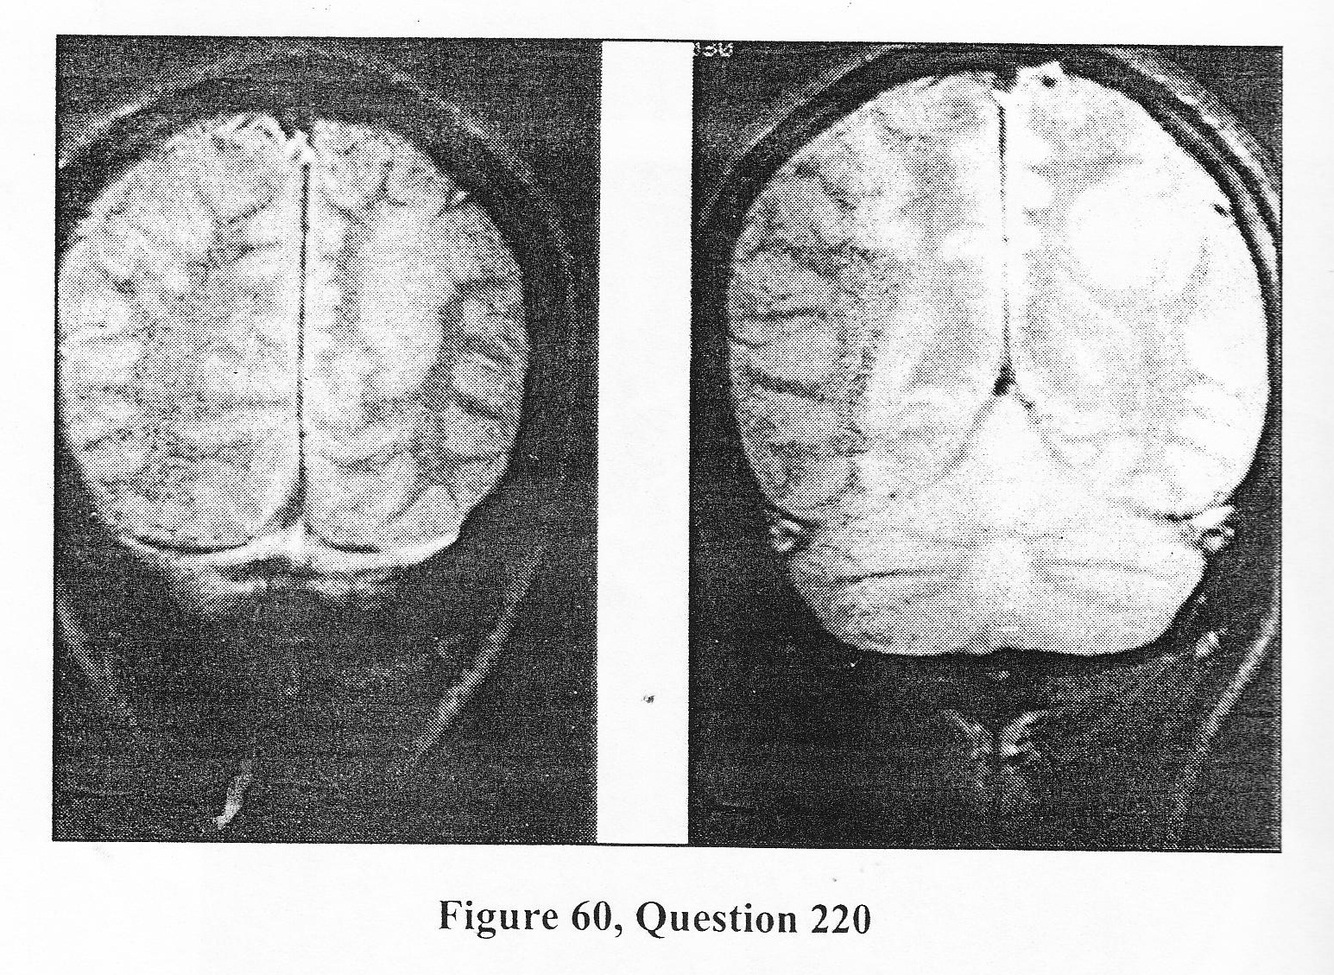

A 15-year-old boy presents with progressively medically refractory epilepsy. Exam revealed a mild hemiparesis and hyperreflexia on the right but was otherwise unremarkable. The MR is depicted in Figure 60. 220. What is the MOST LIKELY diagnosis?

C. cortical dysplasia

A 15-year-old boy presents with progressively medically refractory epilepsy. Exam revealed a mild hemiparesis and hyperreflexia on the right but was otherwise unremarkable. The MR is depicted in Figure 60. 221. With regard to this patient, which of the following statements is TRUE?

D. Dysembryoplastic neuroepithelial tumors often have adjacent areas of cortical dysplasia.